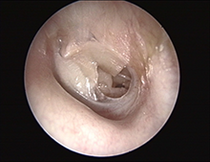

Subtotaler Trommelfelldefekt (rechtes Ohr)